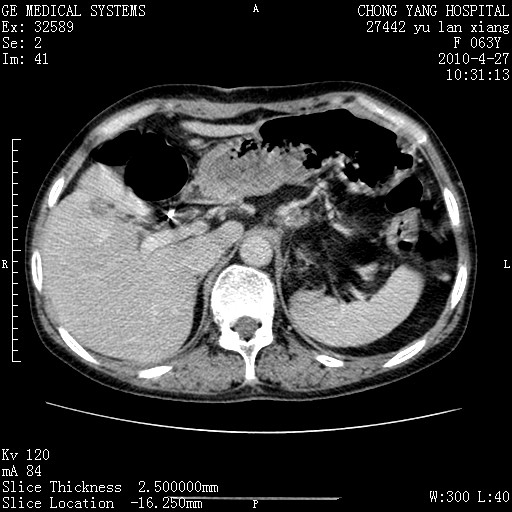

标题: CT26066:F63Y 上腹正中压痛半月,CA199:7400u/ml,MR示胰腺炎伴 [打印本页]

胰腺癌侵犯腹腔动脉干-分支、胃壁、左侧膈肌伴胰周及腹膜后淋巴结转移、胆囊切除术后。

胰腺癌侵犯腹腔动脉干-分支、胃壁、左侧膈肌伴胰周及腹膜后淋巴结转移、胆囊未显影。